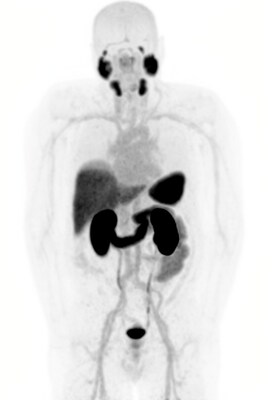

SYDNEY, Jan. 15, 2026 /PRNewswire/ -- Clarity Pharmaceuticals (ASX: CU6) ("Clarity" or "Company"), a clinical-stage radiopharmaceutical company with a mission to develop next-generation products that improve treatment outcomes for patients with cancer, is pleased to share a number of updates on the SECuRE trial following an SRC meeting. The SRC has recommended that the trial continue with the Cohort Expansion Phase (Phase II) as planned with no modifications to the protocol. The interim results assessed by the SRC were collected from nine participants enrolled in the cohort that had evaluable data by the cut-off date of the 25th of November 2025 and continue to show promising efficacy and a favourable safety profile of 67Cu-SAR-bisPSMA. The majority of the nine participants had bone metastasis at enrolment (66.7%) and received multiple lines of previous treatments (more than 5 previous anti-cancer regimens, 55.6%). Median PSA prior to 67Cu-SAR-bisPSMA treatment was 18.9 ng/mL (range 1.5-30.2 ng/mL). Six out of these nine participants received at least 2 cycles of 8 GBq of 67Cu-SAR-bisPSMA each, with two of them also receiving concomitant enzalutamide. Of the nine participants included in this SRC analysis, six had at least two PSA results following their 67Cu-SAR-bisPSMA treatment by the data cut-off date. Of these six participants, thus far four (66.7%) showed reductions in PSA of 50% or more (PSA50) and two (33.3%) showed reductions of 80% or more (PSA80). The safety profile of 67Cu-SAR-bisPSMA remains favourable in the Cohort Expansion, with the majority of related AEs being Grade 1 or 2. The most common related AEs were nausea and lymphopenia (observed in three out of nine participants [33.3%], for each AE). The only AE that was Grade 3 or above was lymphopenia observed in three participants, some of whom had bone metastasis at baseline and/or had received multiple lines of therapy, including taxane and an investigational agent, prior to enrolment in the SECuRE study. There have been no overall renal toxicity or electrocardiogram (ECG) changes observed in these participants. In the combination enzalutamide arm, no new AEs (or worsening of AEs) related to 67Cu-SAR-bisPSMA have been observed to date. Trial participant with no detectable disease after 3 cycles of 67Cu-SAR-bisPSMA One of the participants in the Cohort Expansion was a 64-year-old man with bone metastases and baseline PSA of 5.4 ng/mL prior to entering the SECuRE study. Following his first cycle of 67Cu-SAR-bisPSMA, this participant showed a dramatic 95.2% reduction in PSA. He went on to receive 2 more cycles of 67Cu-SAR-bisPSMA and achieved undetectable PSA levels. In a follow-up bone scan and CT no metastatic disease was observed. This participant only exhibited mild (Grade 1) related AEs, most of which were gastrointestinal events, with no haematological or renal AEs observed. The participant reported having excellent quality of life following the treatment. The interim data from this Phase II continues to confirm the favourable safety profile and promising efficacy seen in previous cohorts of the SECuRE trial[1] and supports the continuation of the trial with the aim to progress to a registrational Phase III study. Clarity's Executive Chairperson, Dr Alan Taylor, commented, "SAR-bisPSMA continues generating world-class data in both theranostic and diagnostic trials. The combination of the optimised dimer 'bis' structure with the benefits of copper isotopes, enabled by the proprietary sarcophagine technology, is proving to have created a product that is here to challenge the current treatment and diagnostic paradigms in radiopharmaceuticals. "We have already seen a glimpse of the effects of 67Cu-SAR-bisPSMA through our Dose Escalation cohorts with additional and similar data being generated in the Cohort Expansion phase, demonstrating once again excellent efficacy and safety results of 67Cu-SAR-bisPSMA. "All of the participants with evaluable data treated in the Phase II to date have shown declines in PSA, with the majority showing PSA decreases of more than 50% and mostly having only mild or moderate AEs. Most of these patients have been treated with more than 5 systemic treatment regiments and had bone metastasis prior to entering the SECuRE study. Although the number of participants with evaluable data to date is small, it is incredible to see yet another extraordinary case where a patient who had bone metastasis prior to entering the study achieved undetectable PSA following 67Cu-SAR-bisPSMA treatment, with no disease observed by anatomical and molecular imaging at the last assessments. This participant only experienced mild, transient AEs, most being gastrointestinal, and has reported having excellent quality of life following the treatment. "Importantly, the work we have undertaken during the Dose Escalation Phase is now continuing to provide a strong foundation for us as we look ahead at protocol development and dosing for our Phase III clinical trial and commercialisation. As the participant numbers continue to increase with the trial enrollment, we continue to see very promising responses over and over again, giving us more confidence about the future of this product and its potential for commercialisation in metastatic castration-resistant prostate cancer (mCRPC). With three Fast Track Designations for the SAR-bisPSMA product and positive interactions with the US Food and Drug Administration (FDA) to date, we are working towards bringing this agent to clinicians and their patients around the world through the entirety of the prostate cancer journey, from first diagnosis to late-stage disease. All of these indications, being imaging in pre-definitive therapy and biochemical recurrence, as well as therapy in mCRPC, are blockbuster markets individually for prostate-specific membrane antigen (PSMA) targeted products, with an estimated combined market value of approximately US$10-15 billion by 2030. We are committed to continuing the development of this product, aiming to bring improved diagnostic and treatment options for prostate cancer in various stages of their disease." About the SECuRE trial The SECuRE trial (NCT04868604)[2] is a Phase I/IIa theranostic trial for identification and treatment of participants with PSMA-expressing mCRPC using 64Cu/67Cu-SAR-bisPSMA. 64Cu-SAR-bisPSMA is used to visualise PSMA-expressing lesions and select candidates for subsequent 67Cu-SAR-bisPSMA therapy. The trial is a multi-centre, single arm, dose escalation study with a cohort expansion involving approximately 54 participants in the US. The overall aim of the trial is to determine the safety and efficacy of 67Cu-SAR-bisPSMA for the treatment of prostate cancer. The SECuRE trial consists of the Dose Escalation (Phase I) and Cohort Expansion (Phase II) Phases. Based on the data from the Dose Escalation Phase, which demonstrated a favourable safety profile and efficacy of 67Cu-SAR-bisPSMA, the SECuRE trial progressed to the Cohort Expansion (Phase II) at an 8 GBq dose level as per the SRC recommendation (up to 6 cycles per patient in total)[3]. Cohort 2 of the Dose Escalation phase of the trial, where participants were dosed with 8 GBq of 67Cu-SAR-bisPSMA, demonstrated a very low rate of related AEs while all three participants achieved PSA declines of 80% or more (PSA80)[1]. The Dose Escalation Phase also showed high PSA response rates of the mCRPC in the pre-chemotherapy setting with a favourable safety profile: 92% of pre-chemotherapy participants (12/13) demonstrated PSA drops greater than 35%, PSA reductions greater than 50% were reached in 61.5% (8/13) of participants, and reductions of 80% or more were achieved in 46.2% (6/13) of participants[1]. These results supported the progress of the trial to its Cohort Expansion Phase using 8 GBq multi-dose in participants who had not received chemotherapy in the mCRPC setting. Recruitment is currently ongoing into the Cohort Expansion Phase which will include 24 participants. A subset of participants will be treated with the combination of 8 GBq of 67Cu-SAR-bisPSMA with enzalutamide (androgen receptor pathway inhibitor [ARPI]), in line with the positive results from the Enza-p trial[4] and previous discussions with and advice from key global medical experts in the field of prostate cancer, including the Company's Clinical Advisory Board members, Prof Louise Emmett and Prof Oliver Sartor, as well as the SRC. About SAR-bisPSMA SAR-bisPSMA derives its name from the word "bis", which reflects a novel approach of connecting two PSMA-targeting agents to Clarity's proprietary sarcophagine (SAR) technology that securely holds copper isotopes inside a cage-like structure, called a chelator. Unlike other commercially available chelators, the SAR technology prevents copper leakage into the body. SAR-bisPSMA is a Targeted Copper Theranostic (TCT) that can be used with isotopes of copper-64 (Cu-64 or 64Cu) for imaging and copper-67 (Cu-67 or 67Cu) for therapy. 67Cu-SAR-bisPSMA and 64Cu-SAR-bisPSMA are unregistered products. The safety and efficacy of 67Cu-SAR-bisPSMA and 64Cu-SAR-bisPSMA have not been assessed by health authorities such as the US FDA or the Therapeutic Goods Administration (TGA). There is no guarantee that these products will become commercially available. About Prostate Cancer Prostate cancer is the second most common cancer diagnosed in men globally and the fifth leading cause of cancer death in men worldwide[5]. Prostate cancer is the second-leading causes of cancer death in American men. The American Cancer Institute estimates in 2025 there will be about 313,780 new cases of prostate cancer in the US and around 35,770 deaths from the disease[6]. About Clarity Pharmaceuticals Clarity is a clinical stage radiopharmaceutical company focused on the treatment of serious diseases. The Company is a leader in innovative radiopharmaceuticals, developing TCTs based on its SAR Technology Platform for the treatment of cancers. www.claritypharmaceuticals.com For more information, please contact: